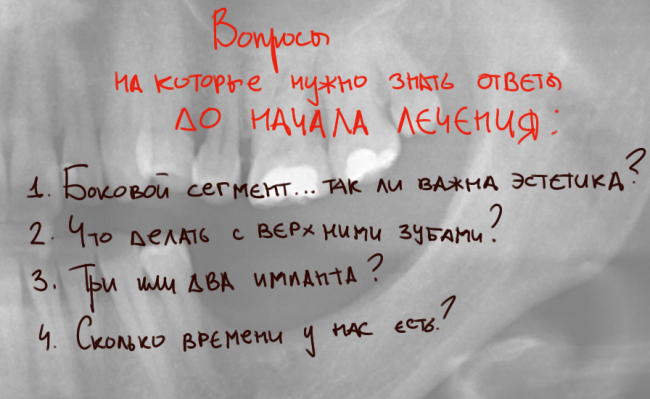

ОДНАКО, до начала лечения, мы должны задать себе и пациентке несколько вопросов:

- Насколько важна эстетика в боковом отделе? От этого сильно зависит объем будущей работы и, разумеется, ее стоимость. В идеале, можно воссоздать зубы, неотличимые от настоящих. Но цена подобного лечения будет в разы выше. чем для получения «приемлемого результата». Мы обсуждаем это с пациенткой и определяемся — эстетика не столь актуальна, ведь эти зубы не видны при улыбке. Гораздо важнее их функциональность и удобство ухода.

- Что делать с верхними зубами? Мы уже ответили на данный вопрос. Параллельно с имплантологическим лечением, мы будем проводить интрузию («втягивание») верхних зубов на их правильные места. Этим займется ортодонт Слива Виктория Рандовна.

- Три или два импланта? При отсутствующих трех зубах мы можем обойтись двумя имплантами. Это будет мостовидный протез с опорой на импланты 35 и 37 зубов. Минусы — мостовидный протез требует более тщательного ухода. Плюсы — он дешевле. При установке трех имплантов мы можем изготовить на каждый имплант одиночную коронку. В этом случае существенно облегчается гигиена и уход за зубами, а сами зубки выглядят более естественно. Минусы — это дороже.

Пока мы не ведем речи об имплантации (она будет через 3 месяца), поэтому у пациентки есть время подумать. В любом случае, остеопластическую операцию мы рассчитываем на область трех зубов, от пятерки до семерки. - Сколько времени у нас есть? Не все готовы ждать год-два для получения идеального результата. Для его достижения, по-хорошему, требуется сначала провести полное ортодонтическое лечение, затем пройти через одну-две операции остеопластики, после чего последует имплантация и, возможно, одна-две операции на слизистой оболочке. Плюс, многоэтапное протезирование. При этом, нас будет преследовать продолжающаяся атрофия кости и слизистой, поэтому, чем дольше лечение — тем сложнее достижим этот идеальный результат. Не говоря уже о финансах. Данный вопрос ОБЯЗАТЕЛЬНО обсуждается с пациентом. Как я уже неоднократно писал, мы делаем то, что хочет пациент, а не то, что хотим мы. В известных пределах, разумеется).